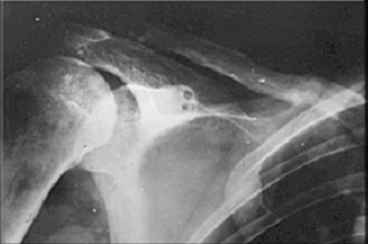

Если заинтересует вариант фиксации трансплантата, представленный в приложении, с удовольствием поделимся опытом.

Л.Соломин